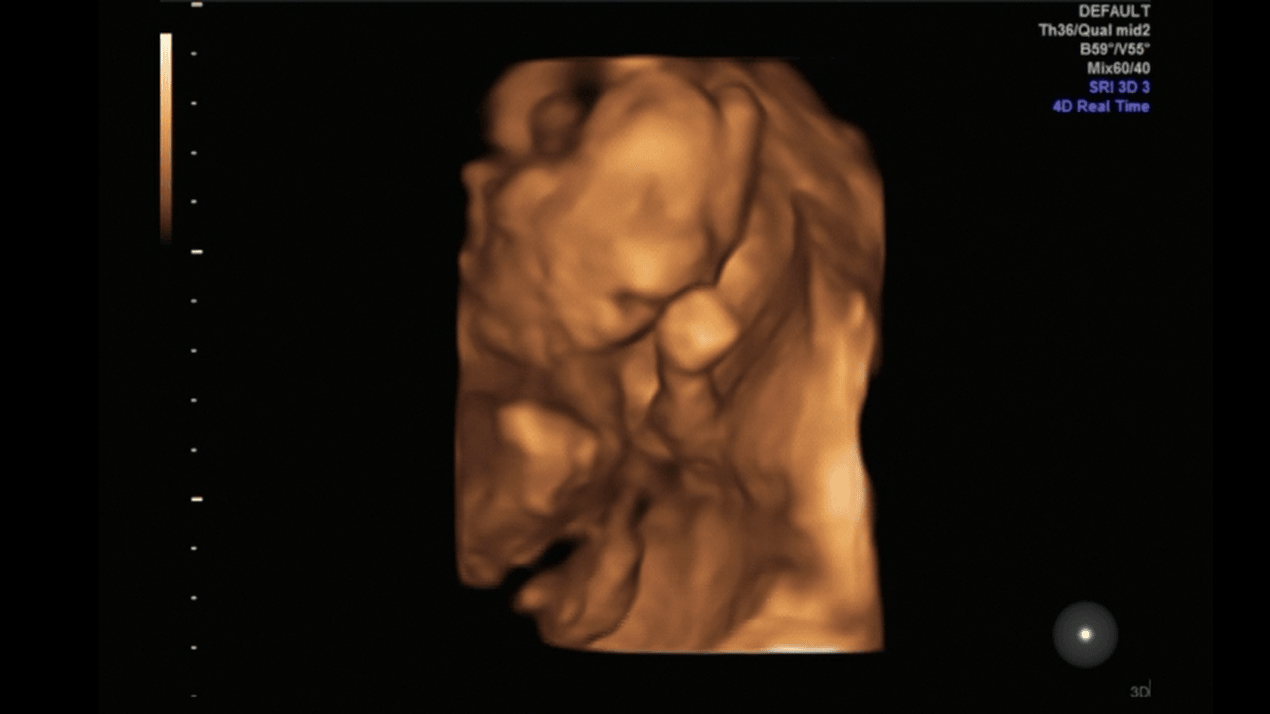

Aha ja chyba pójdę w 29 tygodniu i 6 dniu bo akurat wtedy miesiąc minie od ostatniego usg bo ja na wizycie nie mam usg tylko co miesiąc się zapisuje na takie dokładne mam nadzieje ze nie będzie za wcześnie

to wypadnie 26 kwiecień